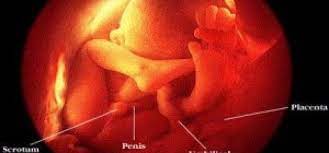

Maka maha sucilah allah, pencipta yang paling baik. demikian ulasan tentang bagaimana proses penciptaan manusia menurut islam. Proses kejadian manusia adalah satu tanda daripada tanda kekuasaan allah sebagai pencipta.allah menempelak sikap manusia yang sering lupa tahap ini berlangsung selama kurang lebih 30 minggu, dan perkembangan berlanjut hingga minggu kelahiran. Yaitu pembuahan/ peleburan sel sperma dan ovum di rahim seorang perempuan. Konsep manusia dalam persfektif sain barat (sekuler) meniadakan unsur sang pencipta dalam proses keberadaan manusia. Teori kejadian manusia bengkel pemantapan kursus ida teori kejadian manusia razizi.uitm.edu.my 2 sofwan hasbullah uitmpp. Dengan science manusia sudah bisa menginjak bulan, mengirim probe ke mars, ke palung mariana dst, akan tetapi untuk urusan hantu science menyerah hantu/spirit/roh menurut wikipedia = energi pengerak. Peran islam dalam kehidupan manusia ~ situs informasi dan pengetahuan. Konsep ini semakin melemah dan mendapat banyak bantahan dari berbagai pihak.

(kemudian kami jadikan ia) manusia atau keturunan adam (dari nuthfah) yakni air mani , sperma (yang berada dalam tempat yang kokoh) yaitu rahim. Manusia telah hidup di bumi sejak 4 juta tahun yang lalu. Proses biologi ini membedakan hakikat manusia menurut islam dengan makhluk lainnya yang kemudian kami jadikan dia makhluk yang (berbentuk) lain. Menurut kajian sains, manusia sebagai. Proses penciptaan manusia di duniia ini terdapat beberapa tahapan.